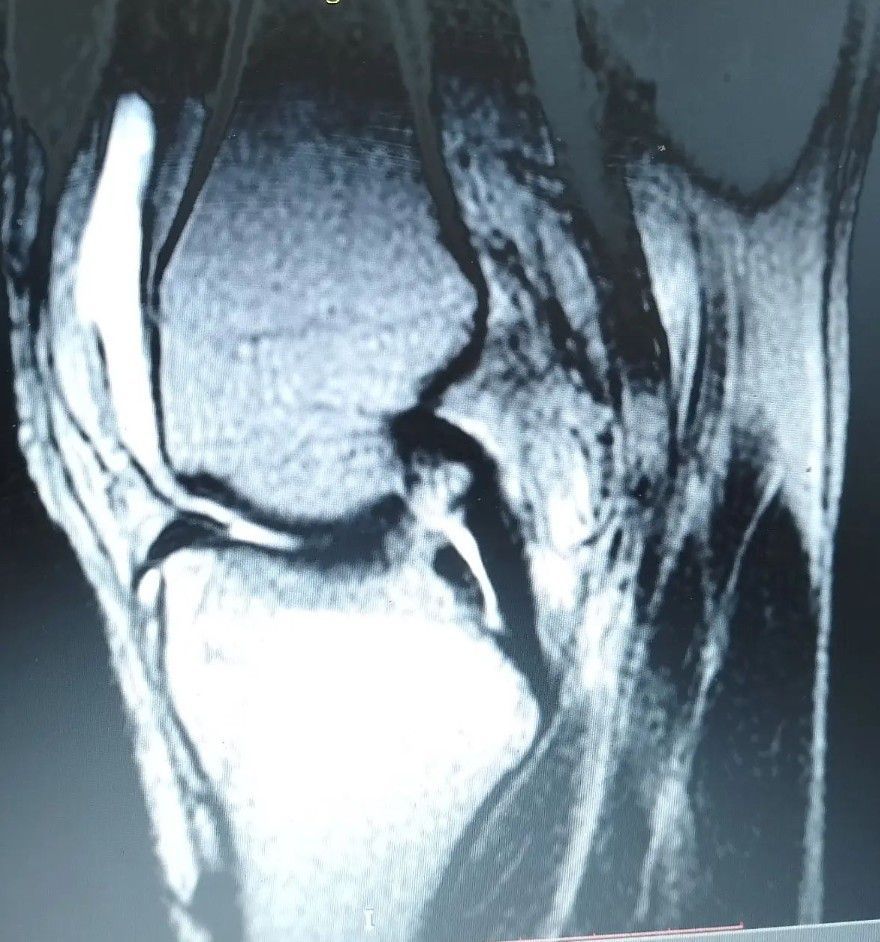

History of trauma while playing soccer. Diagnose it!